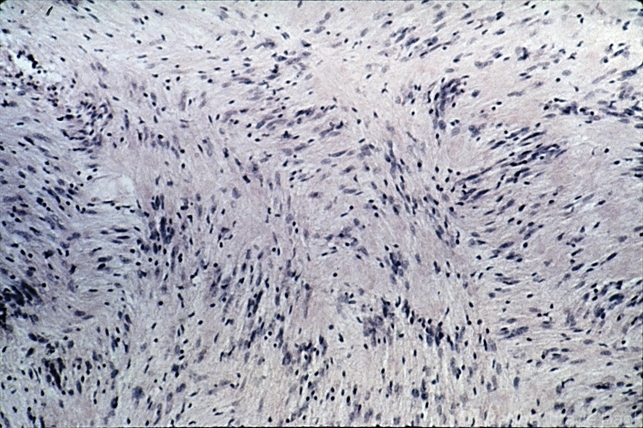

- neurilemmoma

- Neurilemmoma. Antoni A pattern under higher magnification (H&E xlOl).